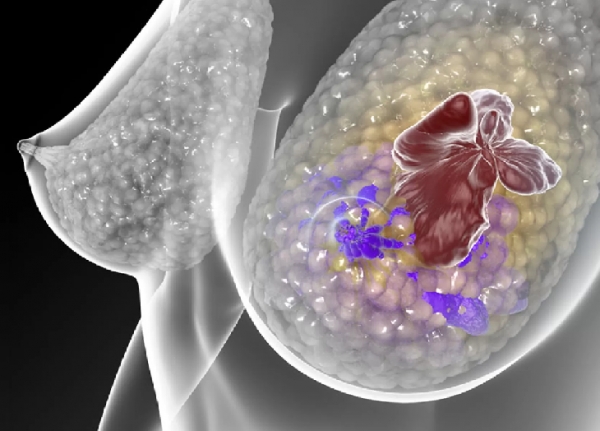

Posicionamento da SBOC sobre câncer de mama metastático triplo-negativo: finalmente um avanço importante no tratamento

Notícias Segunda, 11 Março 2019 17:30Câncer de mama triplo-negativo é relativamente raro e constitui o subtipo mais grave dos cânceres de mama. Embora diversos quimioterápicos tradicionais possam ter algum grau de atividade contra a doença metastática, o controle é pouco duradouro e a expectativa de vida das pacientes é menor que dois anos. Neste contexto bastante sombrio e sem avanços significativos nas últimas décadas, foi apresentado no Congresso da Sociedade Europeia de Oncologia (ESMO Congress 2018) o IMpassion 130, primeiro estudo de fase 3 a documentar benefício significativo de imunoterapia em câncer de mama metastático. Em face da importância do resultado, o estudo foi simultaneamente publicado na mais renomada revista científica médica, o New England Journal of Medicine. Posteriormente novos dados desse estudo (biomarcadores e sobrevida global) foram apresentados no tradicional Simpósio de Câncer de Mama de San Antonio, em dezembro, nos EUA, confirmando o benefício da imunoterapia.

O estudo IMpassion 130 randomizou mulheres com câncer de mama metastático triplo-negativo na primeira linha para receberem tratamento com nab-paclitaxel e placebo ou o mesmo nab-paclitaxel acrescido de atezolizumabe, um imunoterápico moderno. Foram planejadas análises para o grupo total das 451 pacientes de cada braço de tratamento, assim como uma análise exclusivamente para as 185 pacientes de cada braço de tratamento cujos tumores tinham a presença de PD- L1 nos linfócitos que infiltram o tumor. PD-L1 é o alvo da imunoterapia (atezolizumabe) e sua presença tem sido relacionada a maior benefício da imunoterapia em diversos tipos de câncer.

Os resultados do estudo mostraram que, avaliando a população como um todo, havia um controle mais duradouro da doença no grupo tratado com atezolizumabe associado ao nab-paclitaxel, embora a diferença na duração do controle tenha sido modesta. Já na análise das pacientes com PD-L1 positivo (cerca de 40% do total), o benefício em termos de controle da doença foi maior, com uma redução do risco de progressão de 38% (o que significou um ganho de 2,5 meses no controle da doença) em favor da utilização do atezolizumabe. O resultado mais impressionante e animador, no entanto, foi a redução de 38% no risco de morte (representando um ganho de 10 meses em termos de sobrevida global, 25 contra 15,5 meses favorecendo a imunoterapia) no grupo que recebeu atezolizumabe. A toxicidade do tratamento foi leve em ambos os grupos de tratamento (com ou sem imunoterapia).

No contexto de uma doença extremamente grave e praticamente órfã de novas opções de tratamento nas últimas décadas, em função da disponibilidade de ambas as medicações em nosso País (embora aprovadas para outros tipos de tumores) e, principalmente, em face do benefício significativo que este tratamento pode proporcionar às pacientes, a Sociedade Brasileira de Oncologia Clínica (SBOC) vê fundamentos científicos sólidos para solicitar celeridade na aprovação pelas autoridades regulatórias brasileiras da combinação de nab-paclitaxel e atezolizumabe para o tratamento de pacientes com câncer de mama triplo-negativo metastático, ainda mais agora com a aprovação desta combinação terapêutica pela agência norte-americana de medicamentos, o FDA, ocorrida no dia 08 de Março de 2019. Importante ressaltar a necessidade de assegurar o controle de qualidade na identificação das pacientes triplo-negativo, e também de garantir o acesso e o treinamento dos patologistas para a correta testagem da expressão de PD-L1, pois em tempos de medicina de precisão e de custos elevados do tratamento oncológico a correta identificação garante a medicação certa para a paciente certa.